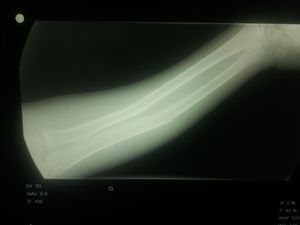

Green stick fracture that typically occurs in children's.

@Dr San Agreed ,we can also see that this is a child's arm because of the non-fused/open epiphyseal plates...

Space between two bones one crack and upper bone band if I'm not wrong

Its not a contour line rather its the cortex , we say 'there is a break or discontinuity in the cortex'